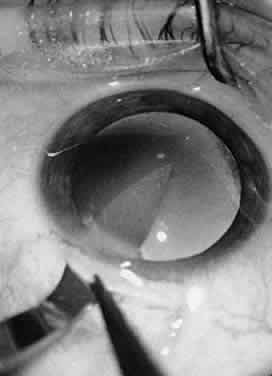

In ophthalmic surgery, viscoelastic materials may be used for many different purposes. Viscoelastic materials are used to protect tissues by providing a protective coating. For example, in the anterior chamber, viscoelastic materials may be used to protect the endothelium during phacoemulsification. Viscoelastic materials also may be used to stabilize a space within the eye or to occupy a virtual space within the eye. Viscoelastic materials may be used to reform the capsular bag after cataract extraction, aiding in the insertion of IOLs (Fig. 31). Additionally, these materials may be used to separate adherent tissue layers when they are introduced through a cannula to lyse synechiae. In some instances, the viscoelastic material may be used to reappose tissues, for example, to replace a detached Descemet's membrane. Finally, a viscoelastic material may be used to occlude or seal the anterior chamber. This technique can be useful during repair of corneal lacerations or when applying tissue adhesive for small corneal perforations.10

Fig. 31. A viscoelastic material may be used to reform the capsular bag after cataract extraction. The viscoelastic material is used to stabilize a space within the eye or to occupy a potential space.

Various viscoelastic materials are currently in use. Largely, the various types of viscoelastic materials differ from one another in their molecular weight. For example, Viscoat brand viscoelastic has a higher molecular weight and therefore might be used when the surgeon needs to stabilize a space within the eye or to occupy a potential space within the eye. The higher molecular weight of the material enables more effective filling of the space and better maintenance of that space. However, the higher molecular weight of the viscoelastic makes it more difficult for the surgeon to remove the material from within the eye. Retained viscoelastic material has long been known to cause decreased function of the trabecular meshwork with a resultant increase in IOP. In the end, the surgeon must weigh the benefits of a higher-molecular-weight viscoelastic against the possibility of hindered trabecular outflow.